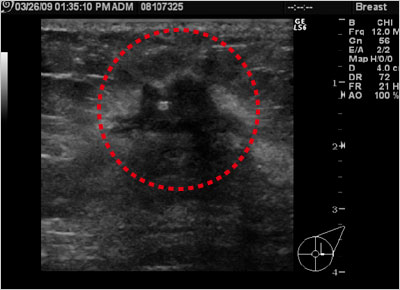

図2 超音波画像

赤枠内の黒い部分が乳がん腫瘤